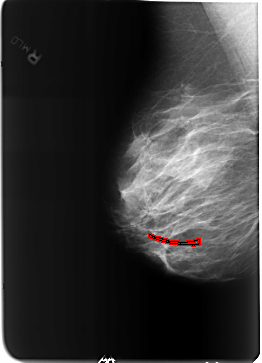

FILE: B_3212_1.RIGHT_MLO.OVERLAY

TOTAL_ABNORMALITIES 1

ABNORMALITY 1

LESION_TYPE CALCIFICATION TYPE VASCULAR DISTRIBUTION N/A

ASSESSMENT 2

SUBTLETY 3

PATHOLOGY BENIGN_WITHOUT_CALLBACK

TOTAL_OUTLINES 1

BOUNDARY